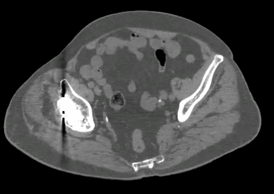

双侧髋关节置换术后(Smart MAR可以减少金属伪影)